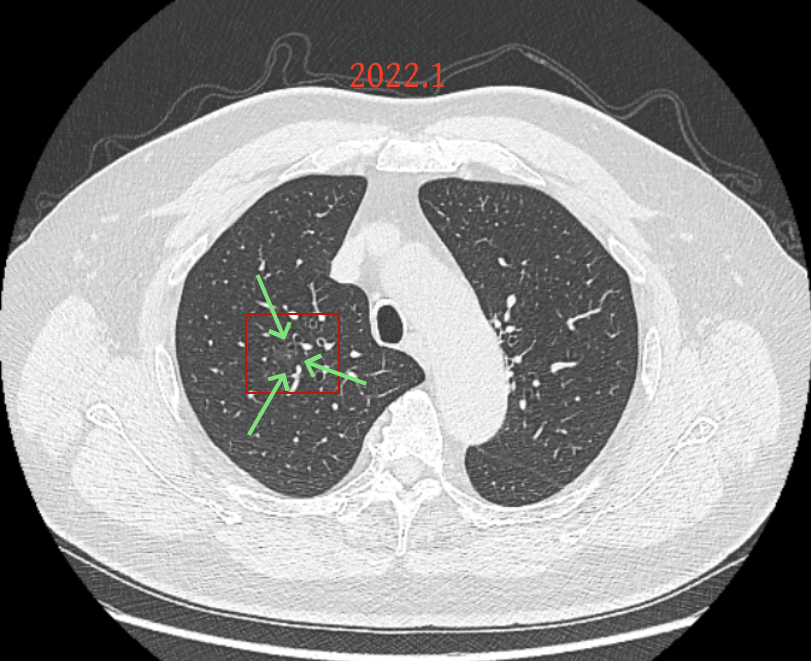

我的意见:

方形的是25年的,红色的主病灶,磨玻璃密度伴少许略偏高点密度,但还说不上典型混合磨玻璃病灶,考虑原位癌或微浸润性腺癌可能性大;蓝色的轮廓与边界欠清,位置靠上叶中央,无法段切或楔切;黄色的多发均淡而纯,分布在两肺。圆形粉色的是主要的两处23年时的样子,对比说不上很明显进展。鉴于若手术得切肺叶,何况两肺他处仍的结节,年纪又74了。我倾向保守点,先6-9个月复查,等进展并风险增加再来考虑怎么办的事。意见供参考!

我的想法是主病灶在右上叶,且多发,而且位置较深,若手术很可能要切且叶,虽考虑是肿瘤范畴的,但由于不管病灶A还是病灶B均仍是磨玻璃密度,没有纵隔窗可见的实性成分,在两肺多发病灶的情况下,适当保守点再随访下,待有进展并风险增高再干预也不至于影响预后。而且根据既往经验,磨玻璃密度的肺癌基本太会短时间内快速进展。

先回顾此前的影像及细节:

病灶没有确切纵隔窗可见的实性成分,但与血管关系较为密切。

微小血管走向病灶,磨玻璃的密度淡而较纯。